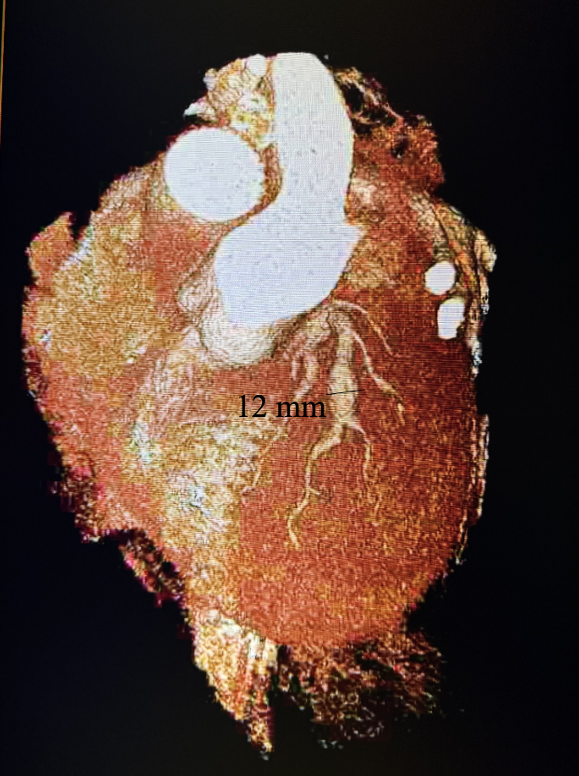

The angiogram revealed multivessel giant coronary aneurysms. The left anterior descending (LAD) coronary artery had an 11 mm proximal-to-mid artery long aneurysm involving the first diagonal branch (Figure 1). The circumflex artery had a proximal giant aneurysm measuring 24 mm, with very little visualization of distal vessel (Figure 2). Coronary dye was mostly stagnant in the coronary aneurysm, which did not fill distal vessels well. The right coronary artery (RCA) had the largest giant aneurysm, measuring 45 mm, with an inability to fill any distal vessels (Figure 3).

Subsequently, coronary CT angiography was performed, showing the exact sizing of the aneurysms and patency of the distal vessel, and confirming the multivessel giant coronary aneurysms diagnosis (Figures 4-6). A cardiothoracic surgery opinion was obtained, but no surgical options would be of benefit per surgical service, since there was no obstructive disease. The patient’s underlying cardiomyopathy was likely due to chronic micro thrombo-embolic phenomena from the coronary aneurysms. It was determined that the patient would be best treated with long-term oral anticoagulation and GDMT for heart failure.